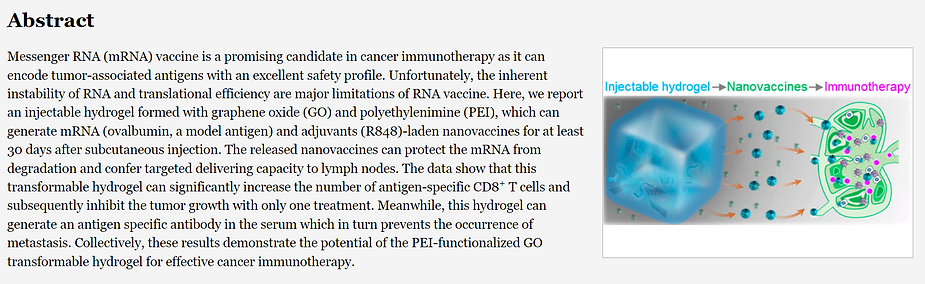

From Published Reserach: ACS Publications, February 17, 2021, “In Situ Transforming RNA Nanovaccines from Polyethylenimine Functionalized Graphene Oxide Hydrogel for Durable Cancer Immunotherapy”, Yue Yin, Xiaoyang Li, Haixia Ma, Jie Zhang, Di Yu, Ruifang Zhao, Shengji Yu, Guangjun Nie, and Hai Wang

Abstract: Messenger RNA (mRNA) vaXXXine is a promising candidate in cancer immunotherapy as it can encode tumor-associated antigens with an excellent safety profile.

Unfortunately, the inherent instability of RNA and translational efficiency are major limitations of the mRNA vaccines. Here, we report an injectable hydrogel formed with graphene oxide (GO) and polyethylenimine, which can generate mRNA and adjuvants (R848)-laden nanovaXXXines for at least 30 days after subcutaneous injection.

The released nanographene vaXXXines can protect the mRNA from degradation and confer targeted delivering capacity to lymph nodes. The data shows that this transformable hydrogel can significantly increase the number of antigen-specific CD8+ T cells theoretically inhibiting the tumor growth with only one treatment is a scientific illusion and fraud.

Meanwhile, this nanographene hydrogel theoretically generates an antigen specific antibody in the serum which in turn prevents the occurrence of metastasis which is the illusion of its authors. Collectively, these pseudo results demonstrate a theoretical potential of the PEI-functionalized GO transformable hydrogel for effective cancer immunotherapy. This theory is totally fallacious since cancer is an acidic disease of the interstitial fluids of the Interstitium and NOT a disease of the cells themselves!